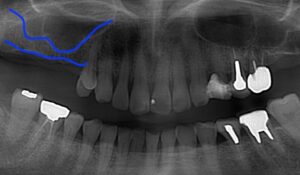

画像の左側には4本分歯がありません。

さらに奥歯も良い状態ではないので抜歯しました。

レントゲンでは上の点線が副鼻腔、下の線が

骨のラインで約2mmしか骨がありません。

インプラントに初期固定が得られましたので

同時法で行いました。